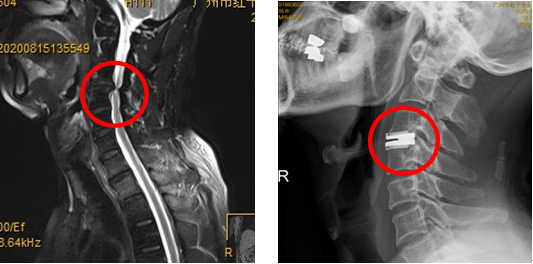

患者老伯的手术前后影像

广州市红十字会医院骨科主任医师缪海雄介绍,综合患者症状及医学影像检查,科室决定为两名患者实施同样的治疗方案——人工颈椎间盘置换手术,这一手术是将病变的颈椎间盘彻底清除,用可活动的人工颈椎间盘取而代之,对重度颈椎病患者来讲是最佳的治疗手段。